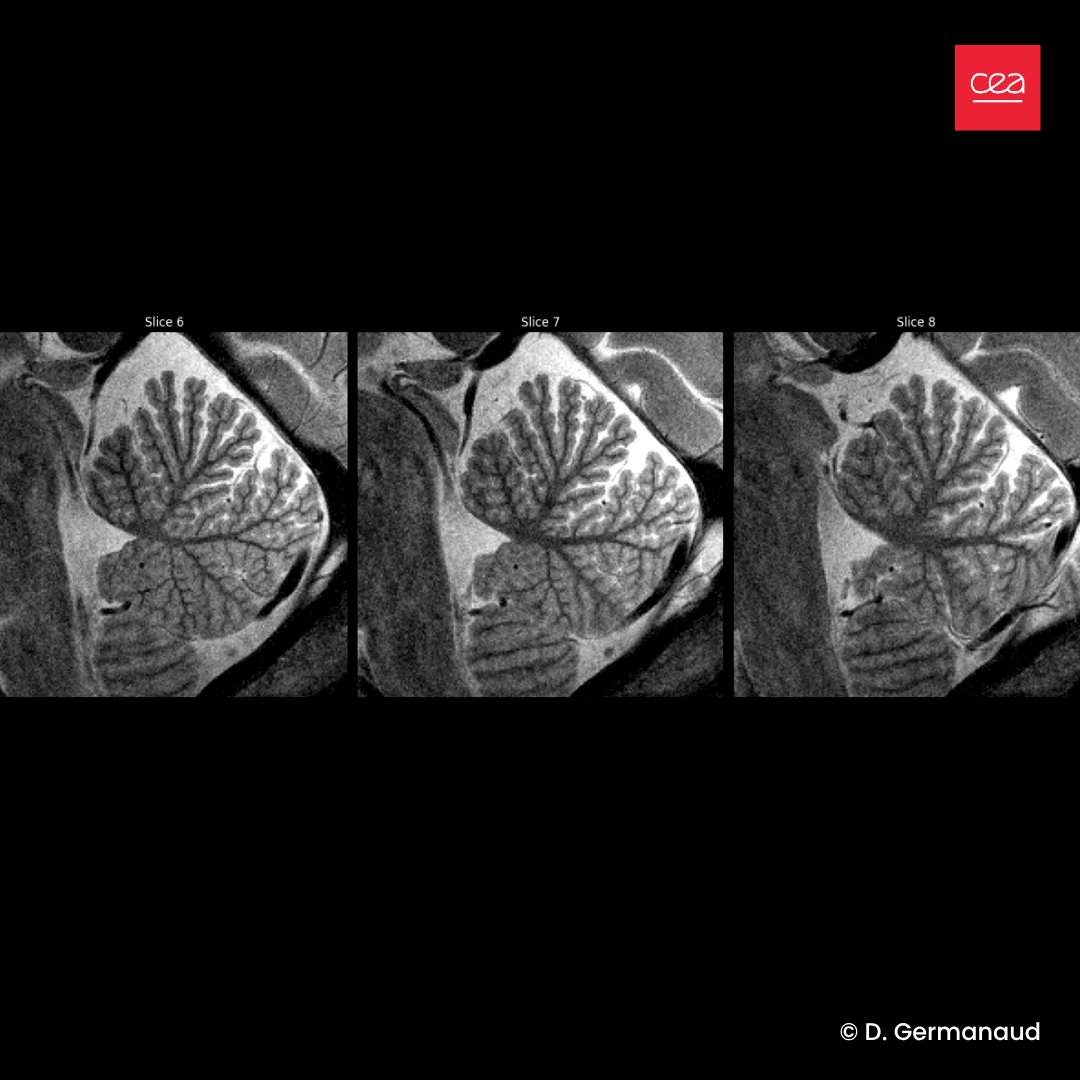

#Cerveau🧠| Le cerveau d’un enfant n'a jamais Ă©tĂ© aussi prĂ©cis🔎 Jusqu’ici, l’IRM Ă  ultra-haut champ 7 teslas Ă©tait rĂ©servĂ© aux adultes. Les Ă©quipes ont rĂ©ussi Ă  adapter cette technologie pour observer le 🧠 en plein dĂ©veloppement chez l’enfant. Plus (+)👉bit.ly/3I8UolX

#Cerveau🧠| Le cerveau d’un enfant n'a jamais Ă©tĂ© aussi prĂ©cis🔎

Jusqu’ici, l’IRM Ă  ultra-haut champ 7 teslas Ă©tait rĂ©servĂ© aux adultes.

Les Ă©quipes ont rĂ©ussi Ă  adapter cette technologie pour observer le 🧠 en plein dĂ©veloppement chez l’enfant.